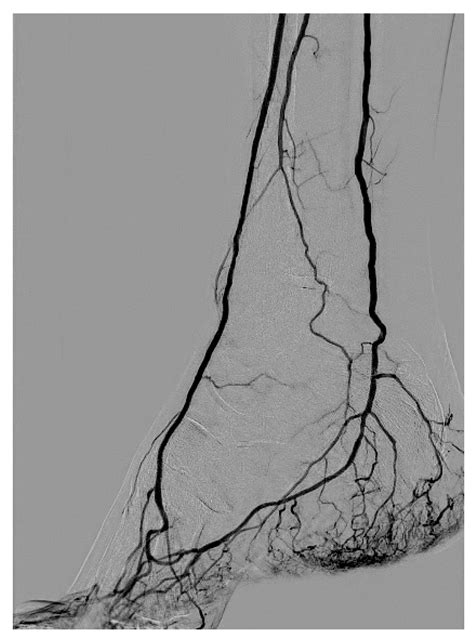

The DSA medical abbreviation stands for Digital Subtraction Angiography. This is a diagnostic imaging technique used to visualize blood vessels in the body. DSA is particularly valuable in identifying blockages, aneurysms, and other vascular abnormalities. The procedure involves injecting a contrast dye into the blood vessels, which is then imaged using X-ray technology. The digital subtraction process enhances the visibility of the vessels by subtracting background structures, providing a clear view of the vascular system.

• Vascular Surgery: Surgeons use DSA to plan and execute procedures for peripheral artery disease, aortic aneurysms, and other vascular issues.

• Case Study 3: Peripheral Artery Disease: A patient with peripheral artery disease undergoes DSA to assess the extent of blockages in the leg arteries. The procedure helps in planning a bypass surgery to restore blood flow.